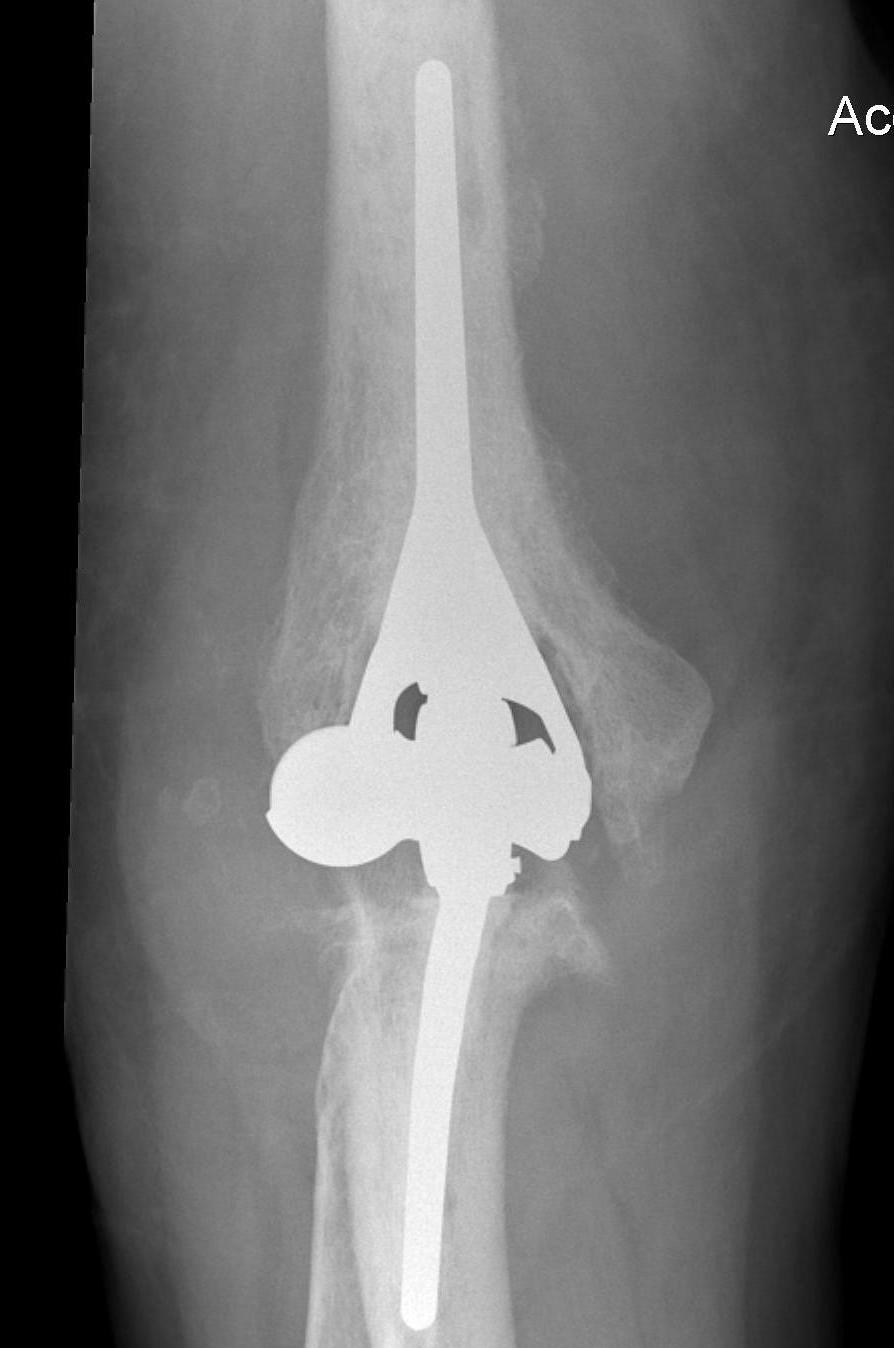

Total Elbow Arthroplasty

Issues

Infection

Triceps - must preserve triceps insertion

Bone stock - deficient humeral columns

Intra-operative fracture - ulna at risk

Constraint

- unlinked require collateral and triceps integrity

- semiconstrained - linked pin and bushing with anterior humeral flange

Results

- systematic review of 38 studies and 2118 patients with TEA for RA

- 7 year follow up

- implant failure 16%

- complication rate 25%

- young patients and unlinked design of TEA most at risk of aseptic loosening